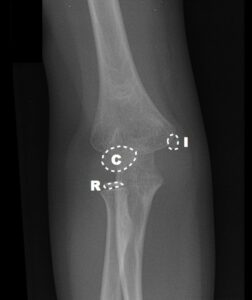

Bu noktaların ortaya çıkma zamanı tahmin edilebilir ancak hastadan hastaya, yaşa, cinsiyete, gelişime göre farklılık gösterebileceği unutulmamalıdır. Karşı taraftaki dirsekle karşılaştırılması patolojik görünüm ya da yapısal farklılığın ayırt edilmesinde yardımcı olur. Bu kemikleşme merkezlerinden ilk ortaya çıkanı Kapitulumdur. Ortaya çıkma sırasına göre “CRITOE” kısaltması kullanılabilir. Kapitulum hariç bu merkezler kızlarda erkeklere göre daha erken görülmektedir.

[toggle title=”Radiokapitellar Hat” state=”close”]

AP, Lateral ve Oblik grafilerde radius başının ortasından geçecek şekilde çekilen çizgi kapitulumun ortasından geçmelidir.

Bu hat üzerinde herhangi bir sapma radius başı çıkığını düşündürür. Bunun dışında lateral kondil kırıklarında da bu hat üzerinde bozulma görülebilir.

Radiokapitellar Hat Kapitulumun medialinde kalmış